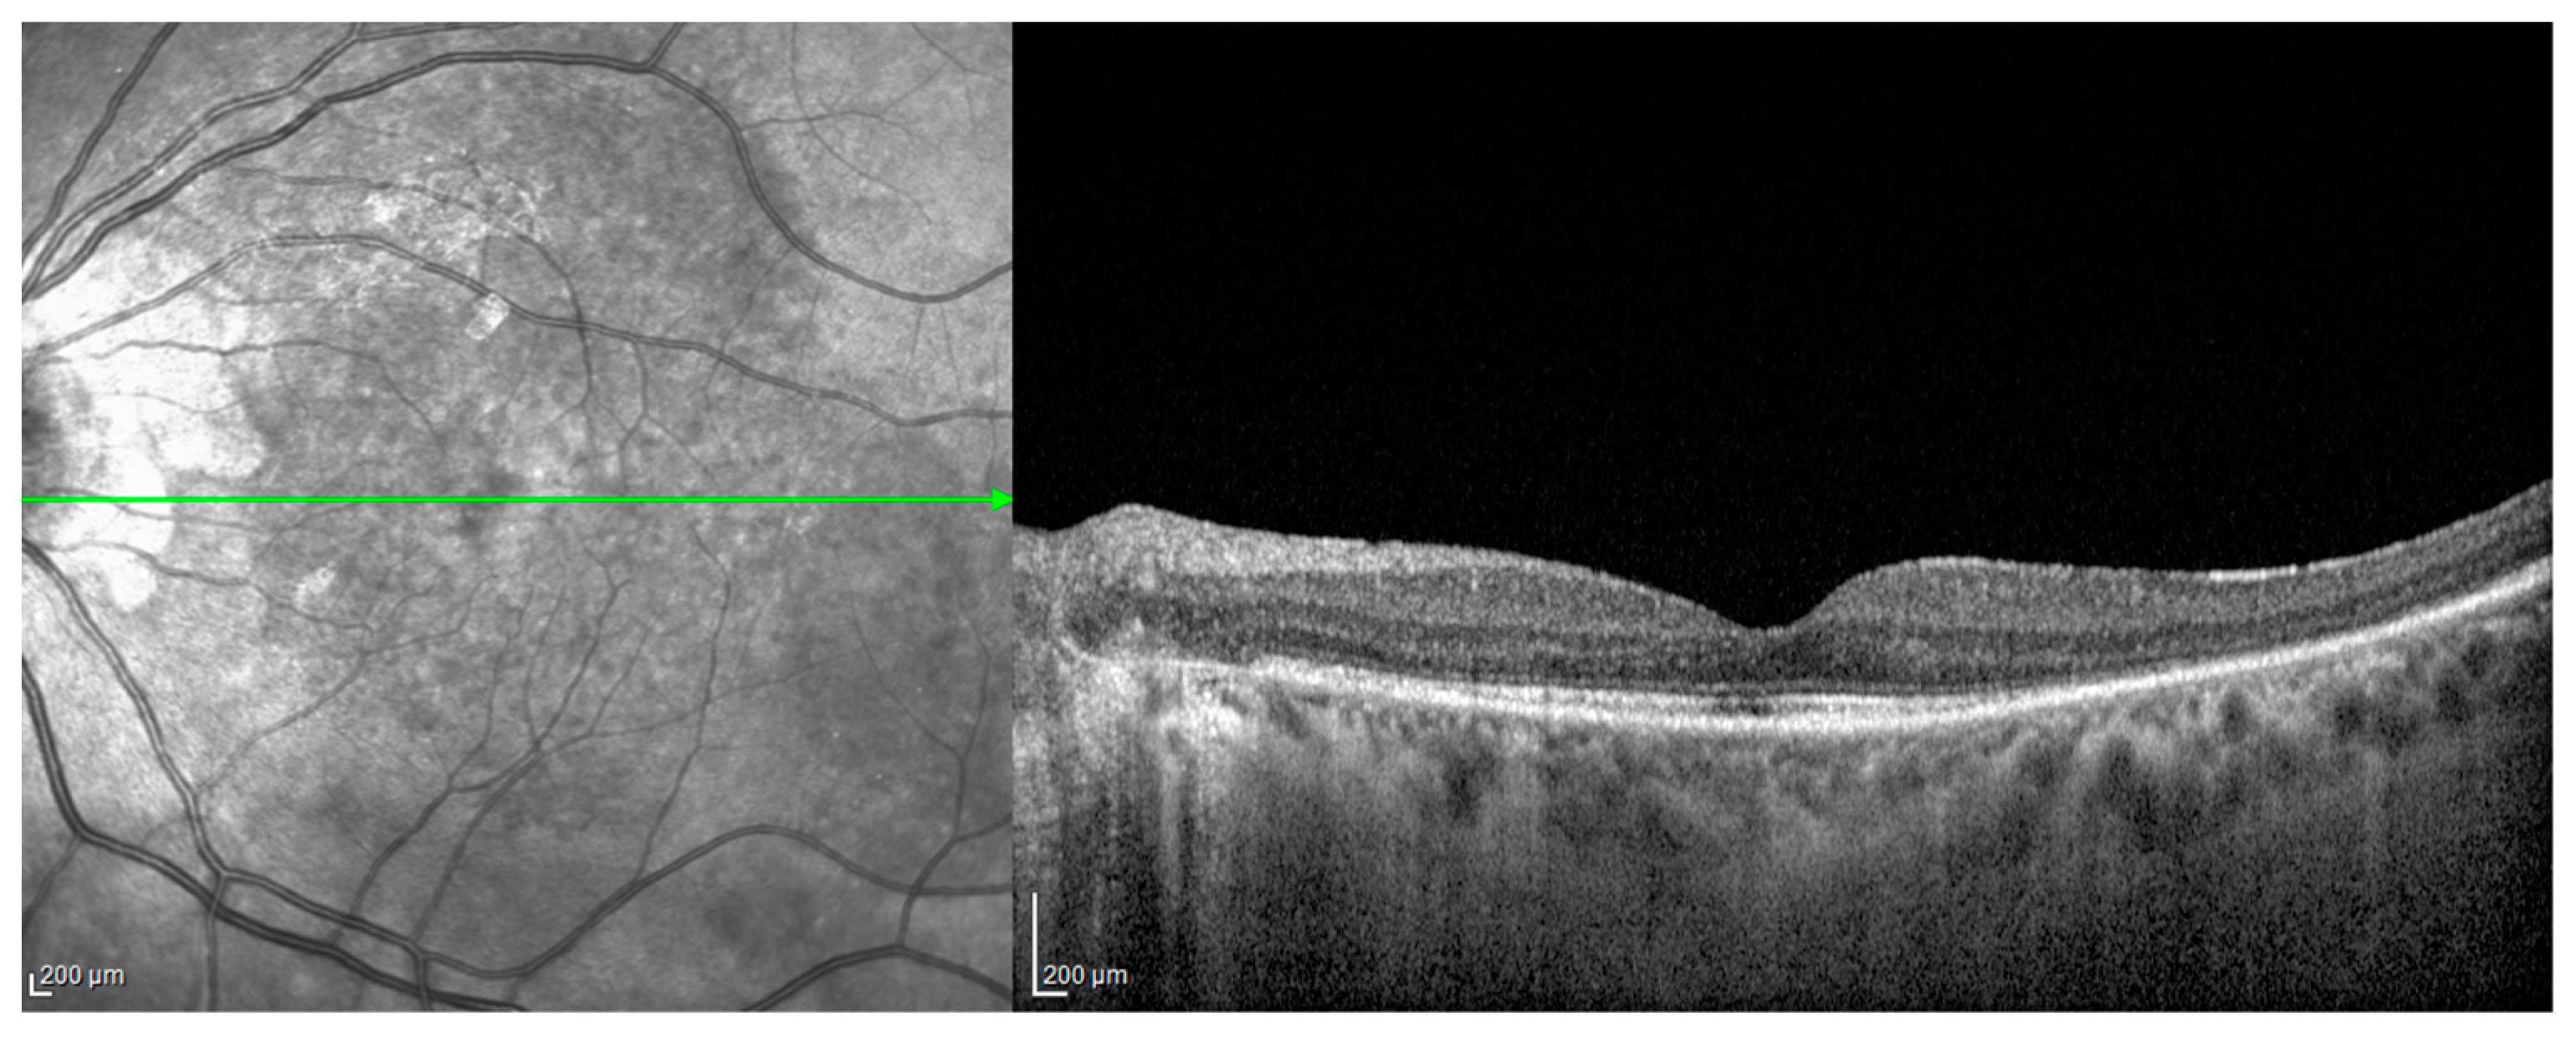

- Acute uveitic stage: This appears a few days after the prodromal phase and lasts for several weeks. During this period, the patient mainly complains of blurred vision, pain and central scotoma, and most patients present with bilateral posterior uveitis. The first sign is the thickening of the posterior choroid manifested as an elevation of the peripapillary retinochoroidal layer, hyperaemia and oedema of the optic disc [31,32] and circumscribed retinal oedema. The choroidal inflammation eventually becomes multifocal with a diffuse breakdown of the RPE causing serous localised elevation of the retina that can rapidly become confluent, leading to a diffuse serous retinal detachment (SRD) [33]. The anterior segment of the eye can be affected immediately after the aforementioned clinical signs in untreated patients. It can be characterised by acute bilateral granulomatous iridocyclitis, mutton-fat keratic precipitates, iris nodules and anterior chamber shallowing due to ciliary body oedema that may lead to acute angle-closure glaucoma.